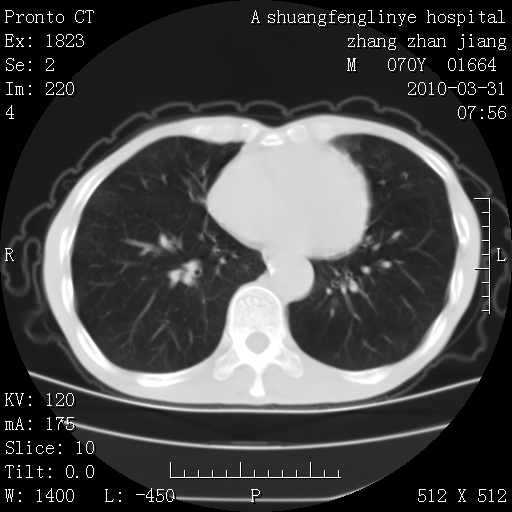

支持,不过左肺中叶那个像陈旧病变的结节要不要单报一下,在图上没看到钙化单报一下放心啊

支持:继发性肺结核伴空洞形成!建议纤支镜检查待出外周围型肺癌可能!

1)两肺上叶继发性肺结核并左肺上叶空洞形成。2)冠状动脉及主动脉钙化。